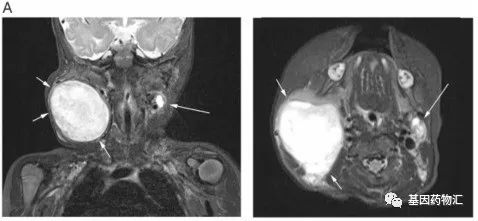

肉瘤靶向治疗,肉瘤靶向药物拉罗替尼挽救手术、放化疗、靶向无效陷入绝境的患者软组织肉瘤是间充质来源的罕见恶性肿瘤,约占成人癌症的 1%,虽然和肺癌,乳腺癌相比并不常见,但是这是一种异质性极强的复杂肿瘤,目前已知的亚型超过了100种,每一种都具有不同的临床表现。不管是罹患哪一种,晚期患者临床上的治疗方案都非常有限。手术,放化疗,靶向治疗后陷入绝境70岁的M女士,